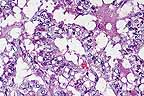

Suppurative bronchopneumonia in a rabbit with a combination of Bordetella bronchiseptica and CAR bacillus. (HE, 200X, 71K)

Bordetella bronchiseptica has been isolated from normal rabbits and young rabbits with respiratory disease. The organism localizes along the cilia of the respiratory epithelium in rabbits, and has been shown to cause ciliostasis in the canine trachea. In chronic infection, it is associated with peribronchial lymphoid hyperplasia, as well as suppurative bronchopneumonia.

Cilia-associated respiratory (CAR) bacillus localizes within the cilia and is associated with peribronchial lymphoid hyperplasia. Natural infections of CAR bacillus in rabbits are reportedly not associated with clinical signs, gross or histologic lesions. Based upon analysis of the 16s mRNA gene sequence, rabbit-origin CAR bacillus is most closely related to members of the genus Helicobacter, white rat-origin CAR bacillus is closely related to the genus Flavobacterium. Serologic tests based upon rat CAR bacillus antigen may be inadequate to detect rabbit CAR bacillus infections.

AFIP Diagnosis: Lung: Bronchopneumonia, suppurative, focally-extensive to diffuse, moderate to severe, New Zealand white rabbit, lagomorph.

Conference Note: Bordetella bronchiseptica is a gram-negative coccobacillus. It is an important cause of respiratory disease in dogs, pigs (atrophic rhinitis), rabbits, and laboratory rodents. Bordetella avium is the agent of turkey coryza and is also pathogenic for quail. Bordetella sp. are most likely transmitted by aerosols, as the organisms are short-lived in the environment. Once introduced to the respiratory tract, the bacteria attach to epithelial cells by fimbriae, filamentous hemagglutinin, and peractin (an adhesin). Once the epithelium is colonized, the bacteria produce several toxins including adenylate cyclase toxin, dermonecrotic toxin, and tracheal cytotoxin. Adenylate cyclase toxin, a member of the RTX toxin family, causes toxic levels of cAMP within macrophages and neutrophils, which prevents the respiratory burst and phagocytic activity. Dermonecrotic toxin is an intracellular product that is released upon lysis of the bacterium and inhibits sodium-potassium ATPase, resulting in vasoconstriction. Tracheal cytotoxin decreases ciliary activity and induces structural changes of ciliated epithelial cells. The loss of ciliated cells causes accumulation of mucus, bacteria, and foreign particles, increasing the likelihood of secondary bacterial infections.

Cilia-associated respiratory (CAR) bacillus causes chronic tracheobronchitis and bronchopneumonia in Iaboratory rodents. In rabbits, the CAR bacillus has been shown to be of minimal clinical importance, causing only mild goblet cell hyperplasia with no inflammatory infiltrate and mild parabronchiolar lymphoplasmacytic hyperplasia with concurrent epithelial cell and/or goblet cell hyperplasia. Rat and rabbit strains of CAR bacillus appear to have significant differences, the rat strain being more closely related to Flavobacterium and the rabbit strain more closely related to Helicobacter. It is not known if the differences in lesions between rodents and rabbits is due to variations in virulence factors, host susceptibility, or both.

In this case, there are myriad silver-staining bacilli among the cilia of the bronchial epithelium. Simultaneous infection of CAR bacillus and Bordetella bronchiseptica have been reported and it has been theroized that this combination increases the severity of the respiratory disease.